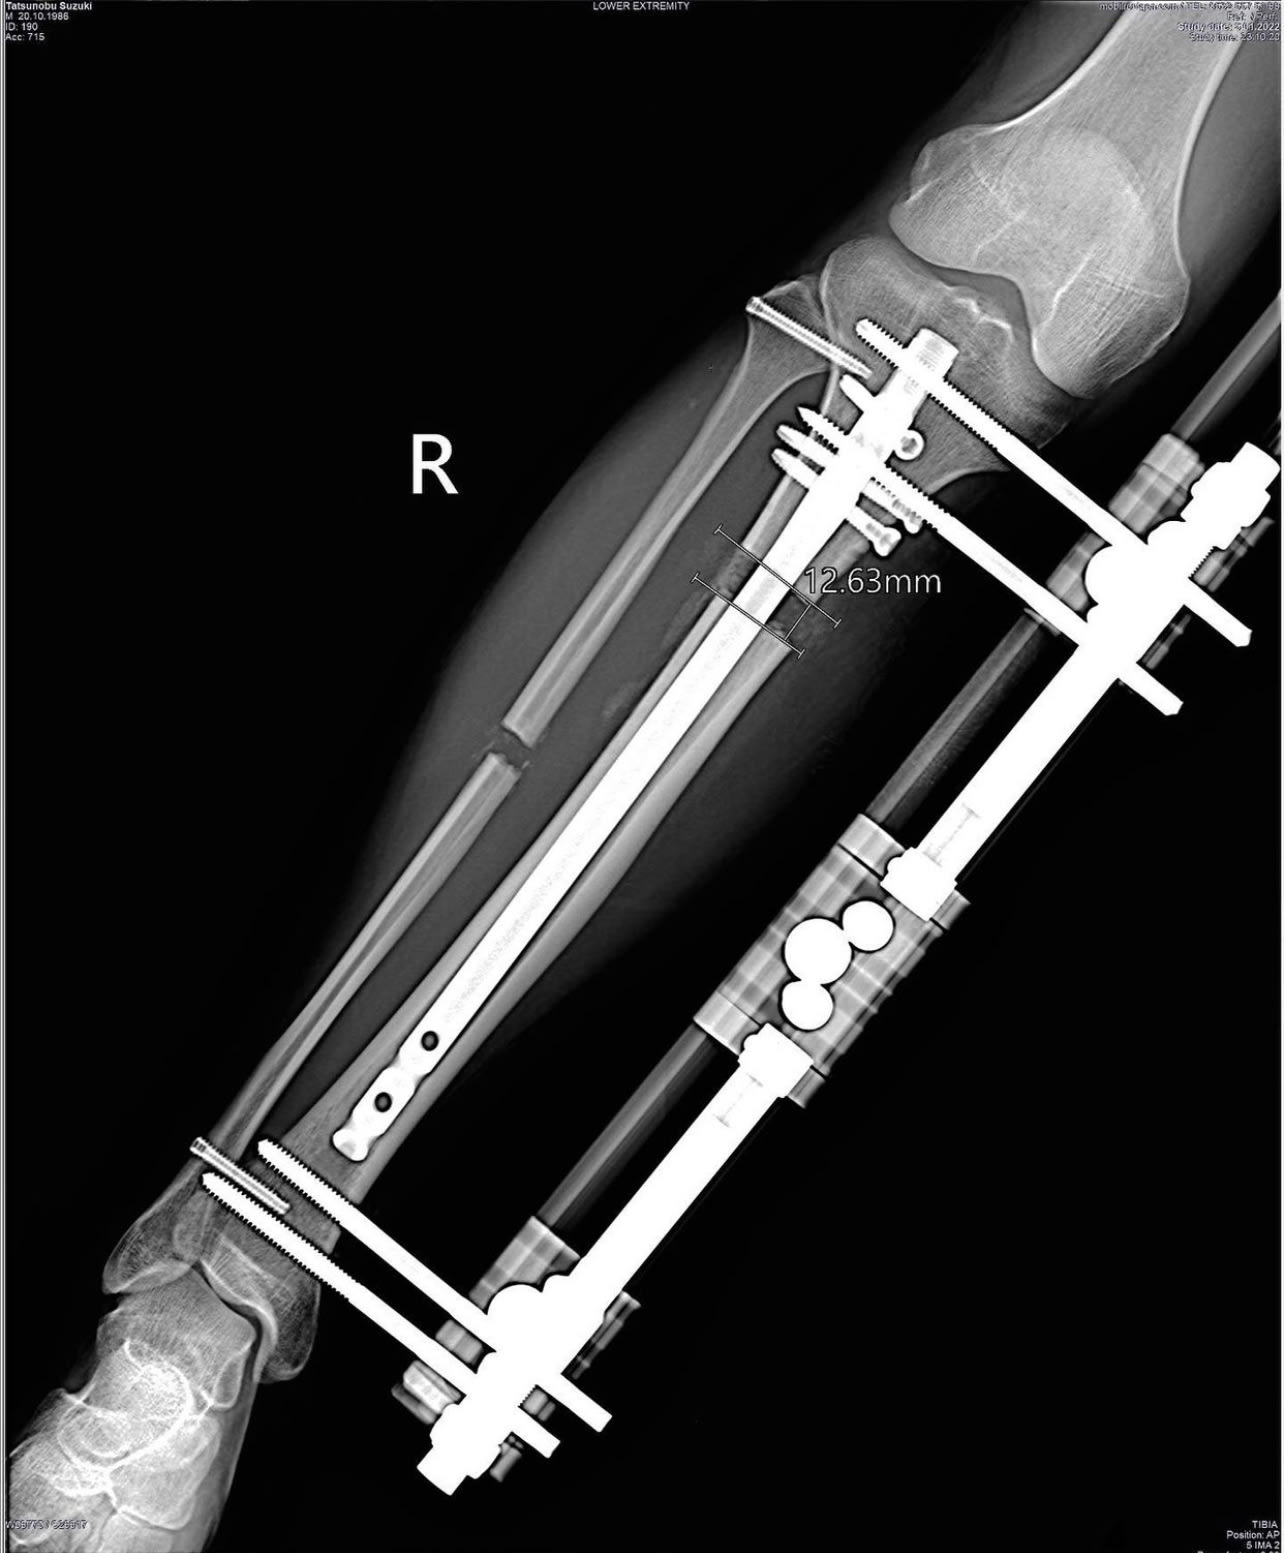

胫骨肢体延长手术动画